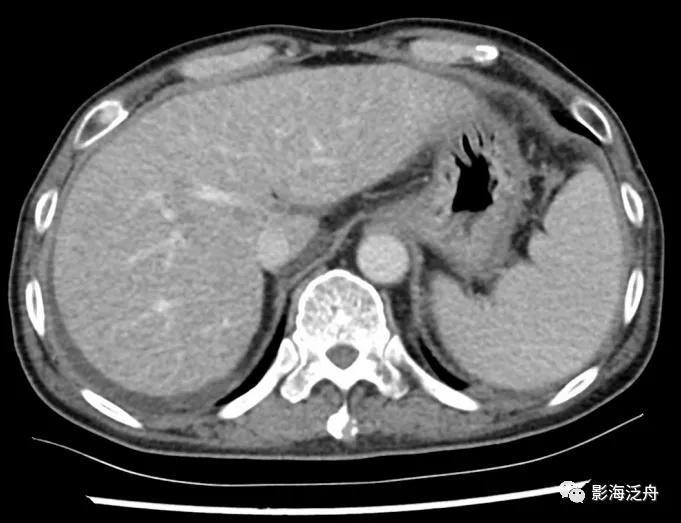

同一患者,又过了3个月复查,可以比较清楚地观察到肝内有很多异常强化灶,边界不清,表明肝脏已经出现弥漫性转移。如果能够提高意识,在第一次复查时就给出异常提示或进一步检查,或许能。。。

另一例乳腺癌导致的肝脏弥漫性转移病例。